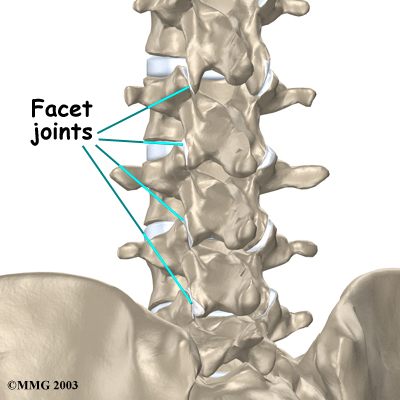

Between the vertebrae of each spinal segment are two facet joints. The facet joints are located on the back of the spinal column. There are two facet joints between each pair of vertebrae, one on each side of the spine. A facet joint is made of small, bony knobs that line up along the back of the spine. Where these knobs meet, they form a joint that connects the two vertebrae. The alignment of the facet joints of the lumbar spine allows freedom of movement as you bend forward and back.

Facet Joints

The surfaces of the facet joints are covered by articular cartilage. Articular cartilage is a smooth, rubbery material that covers the ends of most joints. It allows the bone ends to move against each other smoothly, without friction.